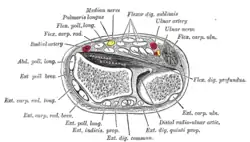

Cross-section through the middle of upper arm. Cross-section through the middle of the forearm.

Cross-section through the middle of the forearm. Transverse section across distal ends of radius and ulna.